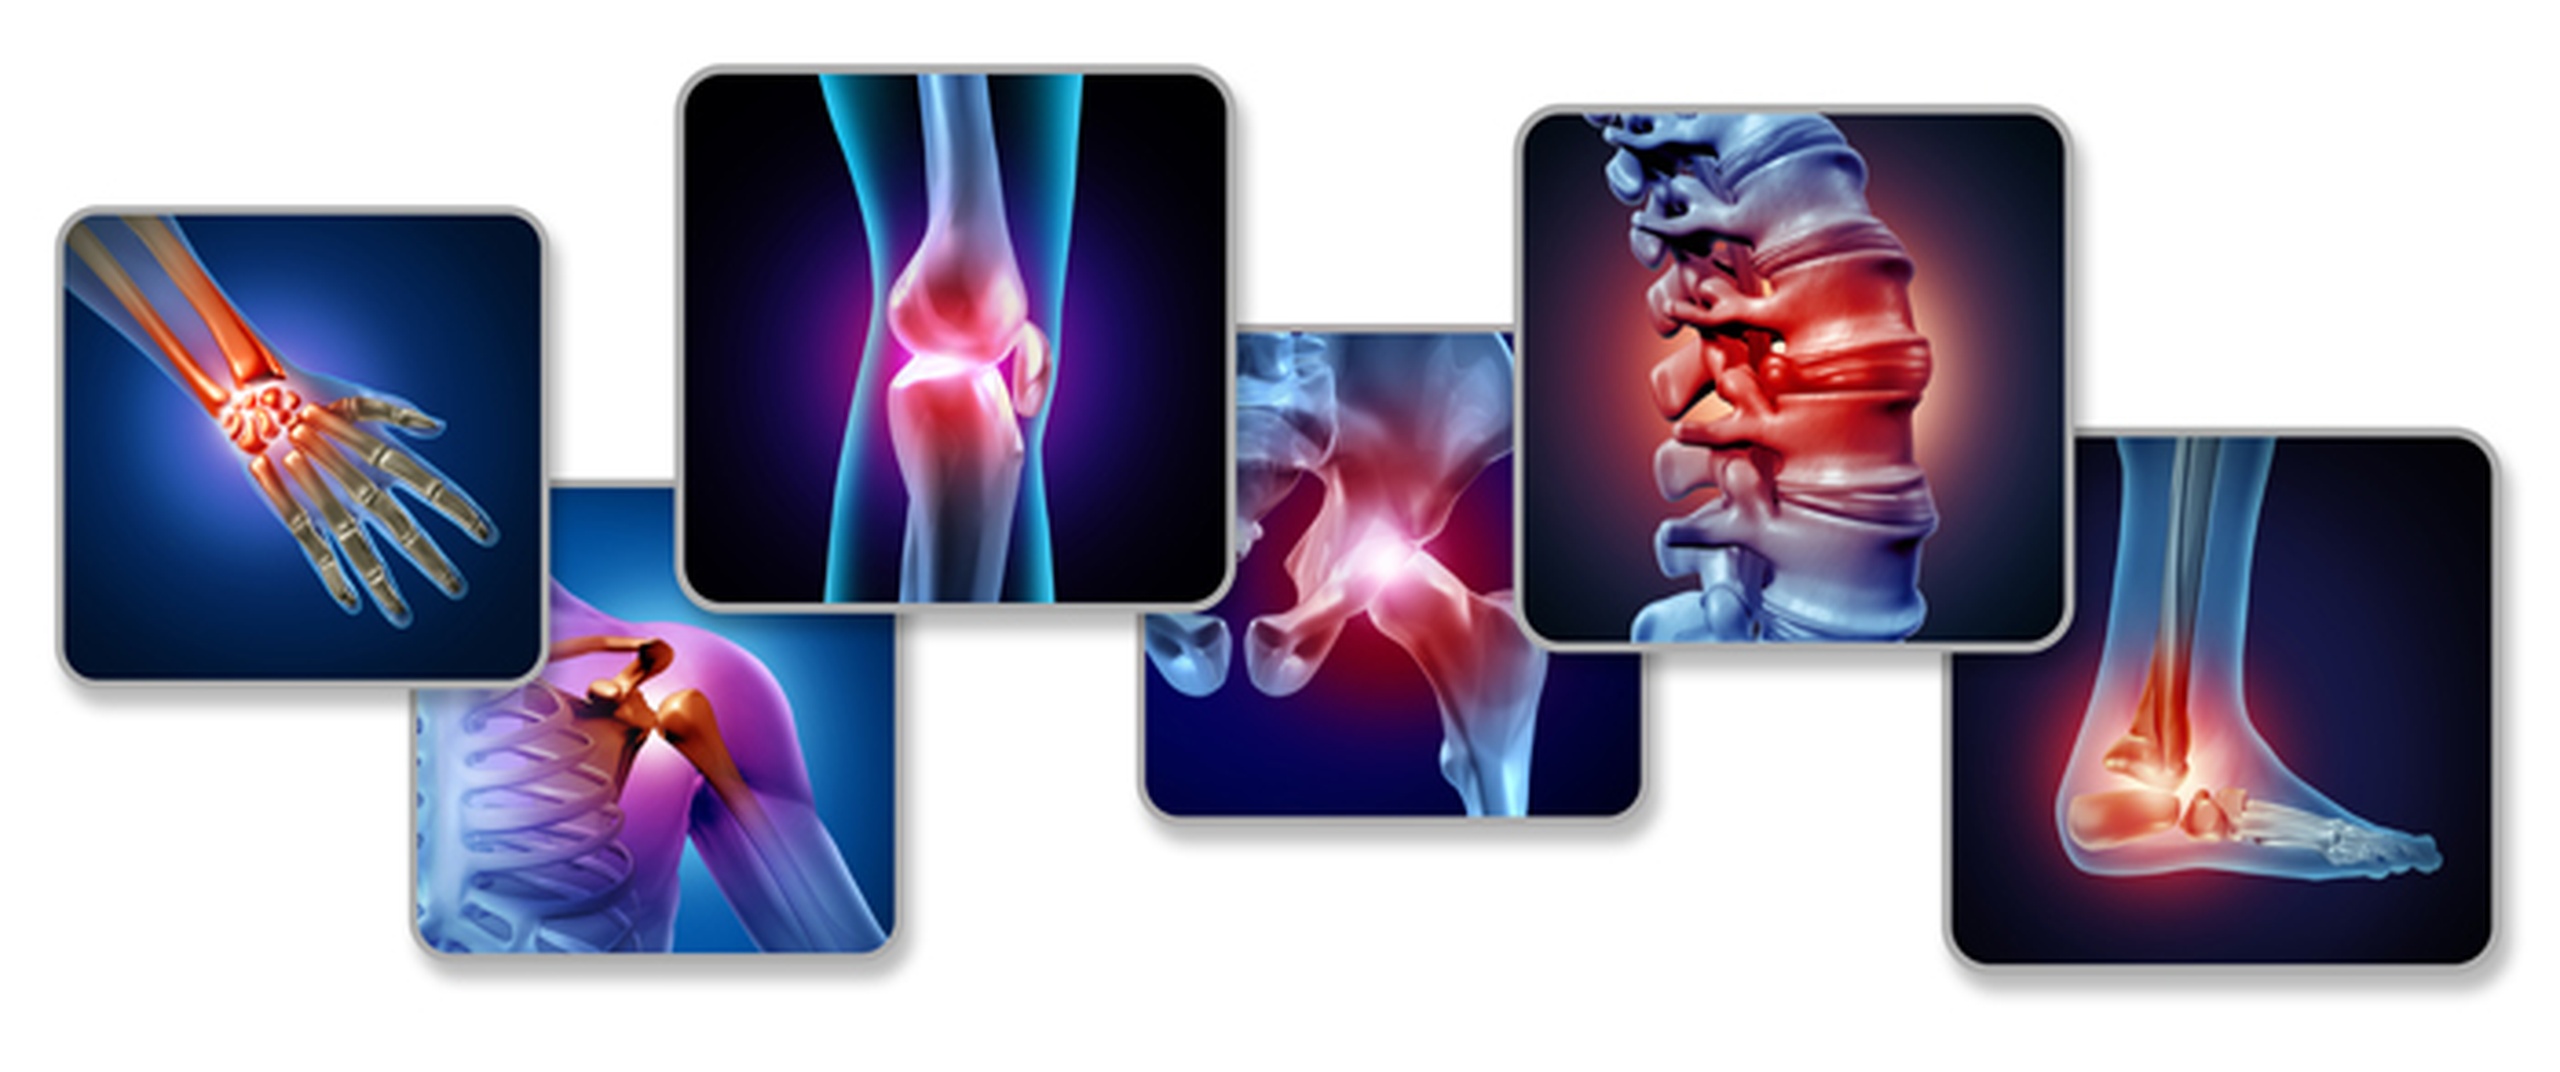

Persistent back or neck pain that radiates to the arms or legs can be difficult to manage without proper treatment. Selective Nerve Root Blocks in Kothrud provide a precise and effective solution to diagnose and relieve nerve-related pain. At Dr. Paradkar’s Ortho Cure and Pain Relief Clinic, we offer advanced Selective Nerve Root Blocks in Kothrud to reduce inflammation and target the exact source of pain without surgery.

This treatment is especially beneficial for conditions like sciatica, slipped disc, and nerve compression. With the expertise of a Non Surgical Orthopedic Doctor in Kothrud, patients receive accurate diagnosis and safe treatment. Our approach to Pain Management in Kothrud ensures faster recovery and long-lasting relief.

Choosing the right treatment can significantly improve your comfort and mobility. Selective Nerve Root Blocks in Kothrud help reduce inflammation around the affected nerve, relieve radiating pain, and improve overall function. It is highly effective for patients suffering from chronic nerve pain and spinal conditions.

The procedure begins with a detailed evaluation of your condition. A targeted injection is administered near the affected nerve root to reduce inflammation and relieve pain. This minimally invasive procedure is quick, safe, and performed with precision.